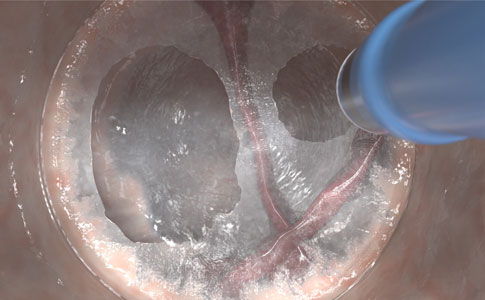

Uzyskaj przestrzeni podśluzówkowej bez konieczności wymiany instrumentu przy użyciu wysokociśnieniowej, bezigłowej, selektywnej tkankowo hydrodyssekcji.

- Bardziej spójne i niezawodne oddzielanie i uzyskaj przestrzeni w tkance podśluzówkowej w porównaniu z konwencjonalną iniekcja igłową, nawet w trudnych warunkach anatomicznych, np. nad fałdem lub zwłóknieniem podśluzówkowym

- Izoluje i odsłania naczynia krwionośne oraz uciska naczynia krwionośne, zmniejszając niebezpieczeństwo krwawienia